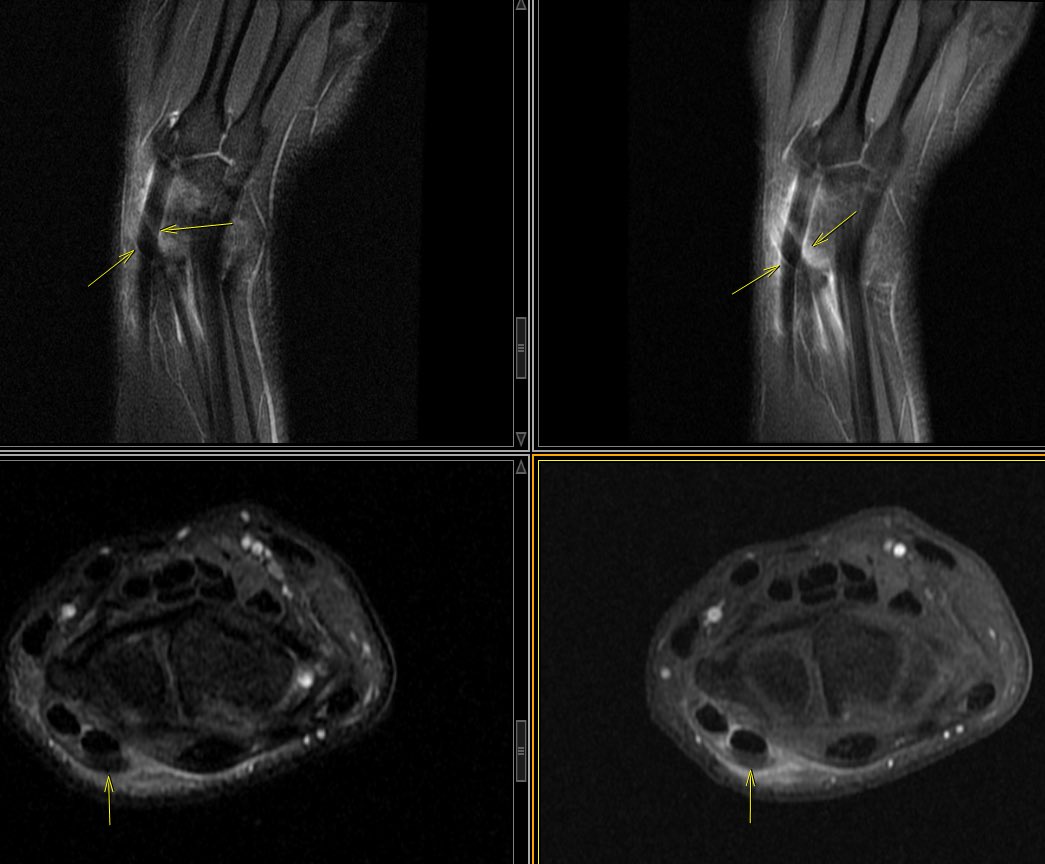

Distal Intersection Syndrome . patient refers pain and “click” over Lister’s tubercle . peritendinous edema and fluid within the tendon sheaths at the intersection point between the 2nd and 3rd (extensor pollicis longus) extensor dorsal tendon compartments

#mskRAD#radiologypic.twitter.com/7Qv9NQVpKo